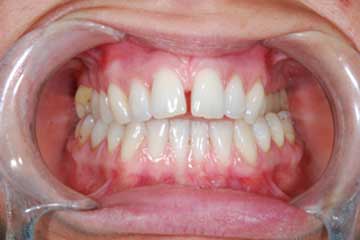

Riabilitazione gnatologica, ortodontica ed estetica

Durata del trattamento: un anno